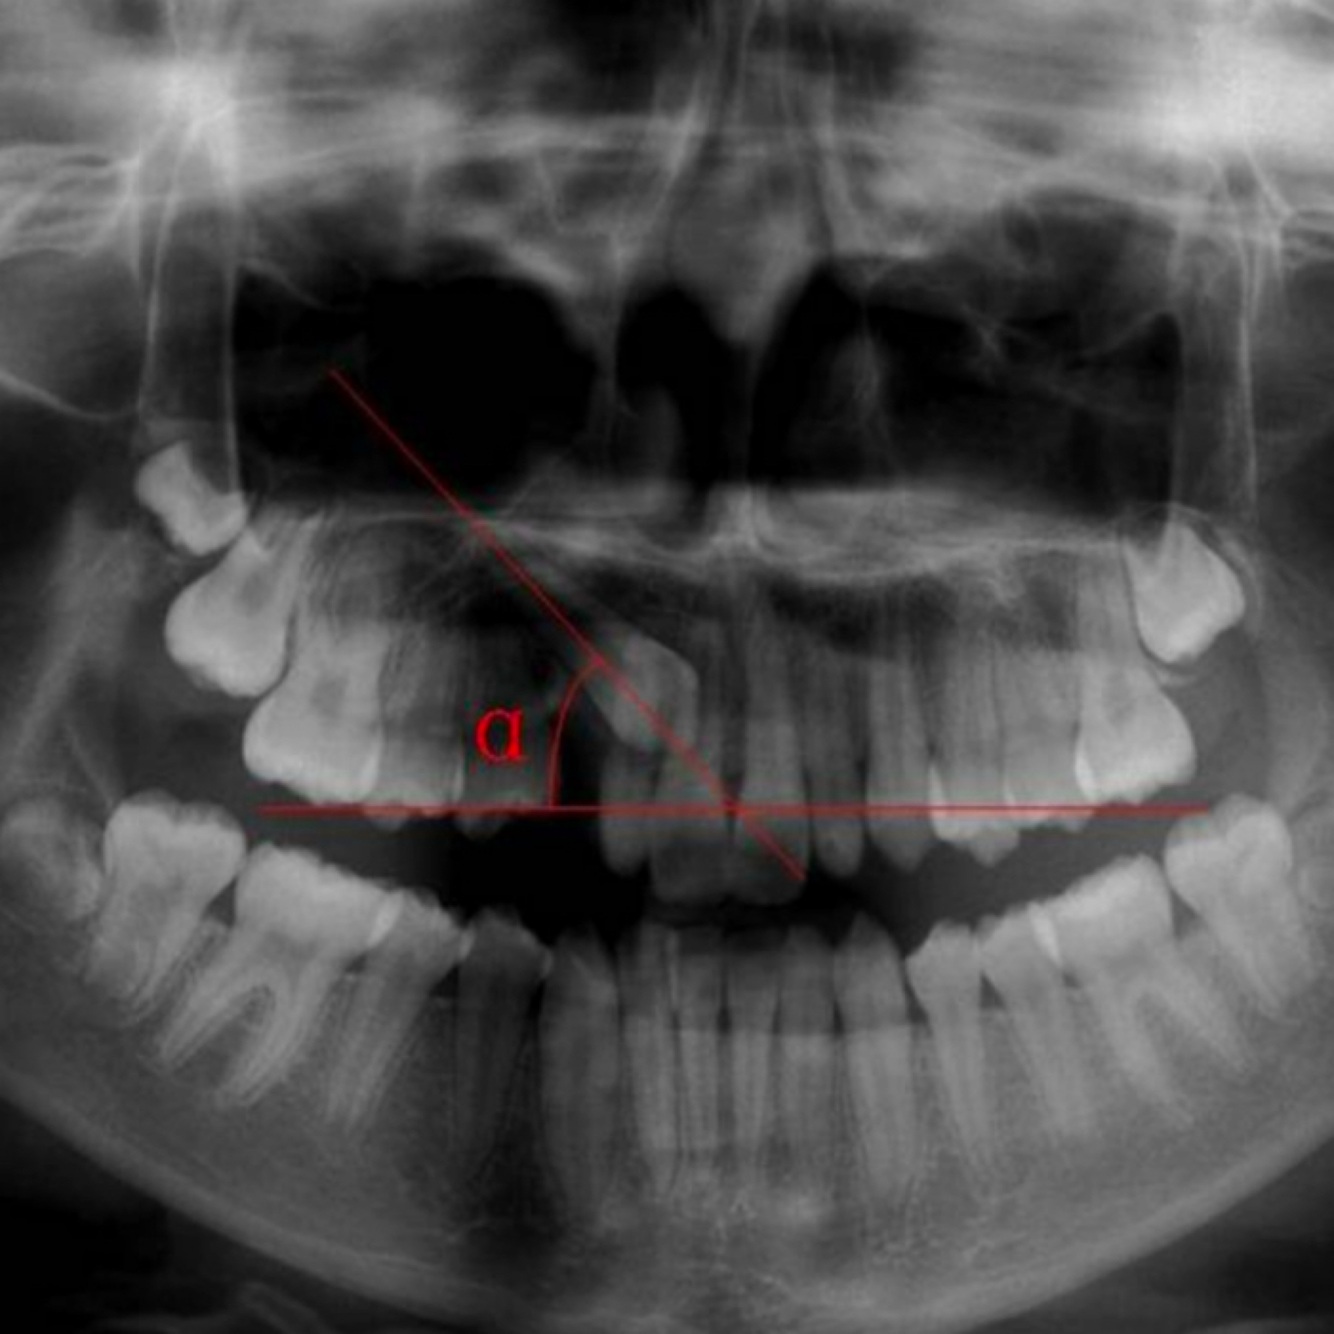

Maxillary canine impaction

• Max canine impaction affects ~2% of pop

• 2/3 cases are palatal, 1/3 labial (arch length discrepancy is thought to be an etiology factor for labially impacted canine)

Preventive extractions of primary canines before the age 11 can normalize permenant canine eruption in:

- 91% cases when the crown is distal to the lateral incisor’s midline

- 64% cases when the crown is mesial to the lateral incisor’s midline

Panormic: angulation of the canine to the occlusal plane is measured. If > or equal to 65 deg, canine is 26x more likely to be labially impacted